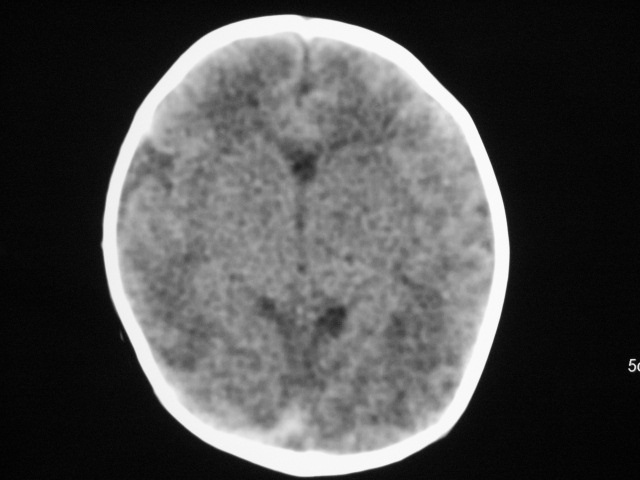

早产儿,1天,饮食呕吐,

双侧额叶见片状低密度灶,皮髓质分界模糊.患儿前囟略饱满,

支持;新生儿缺血缺氧性脑病.请密切结合临床.

患儿头颅ct示:皮质薄,髓质密度减低,脑回宽,脑沟浅,脑室系统无殊,中线结构居中,符合:早产儿颅脑ct改变。